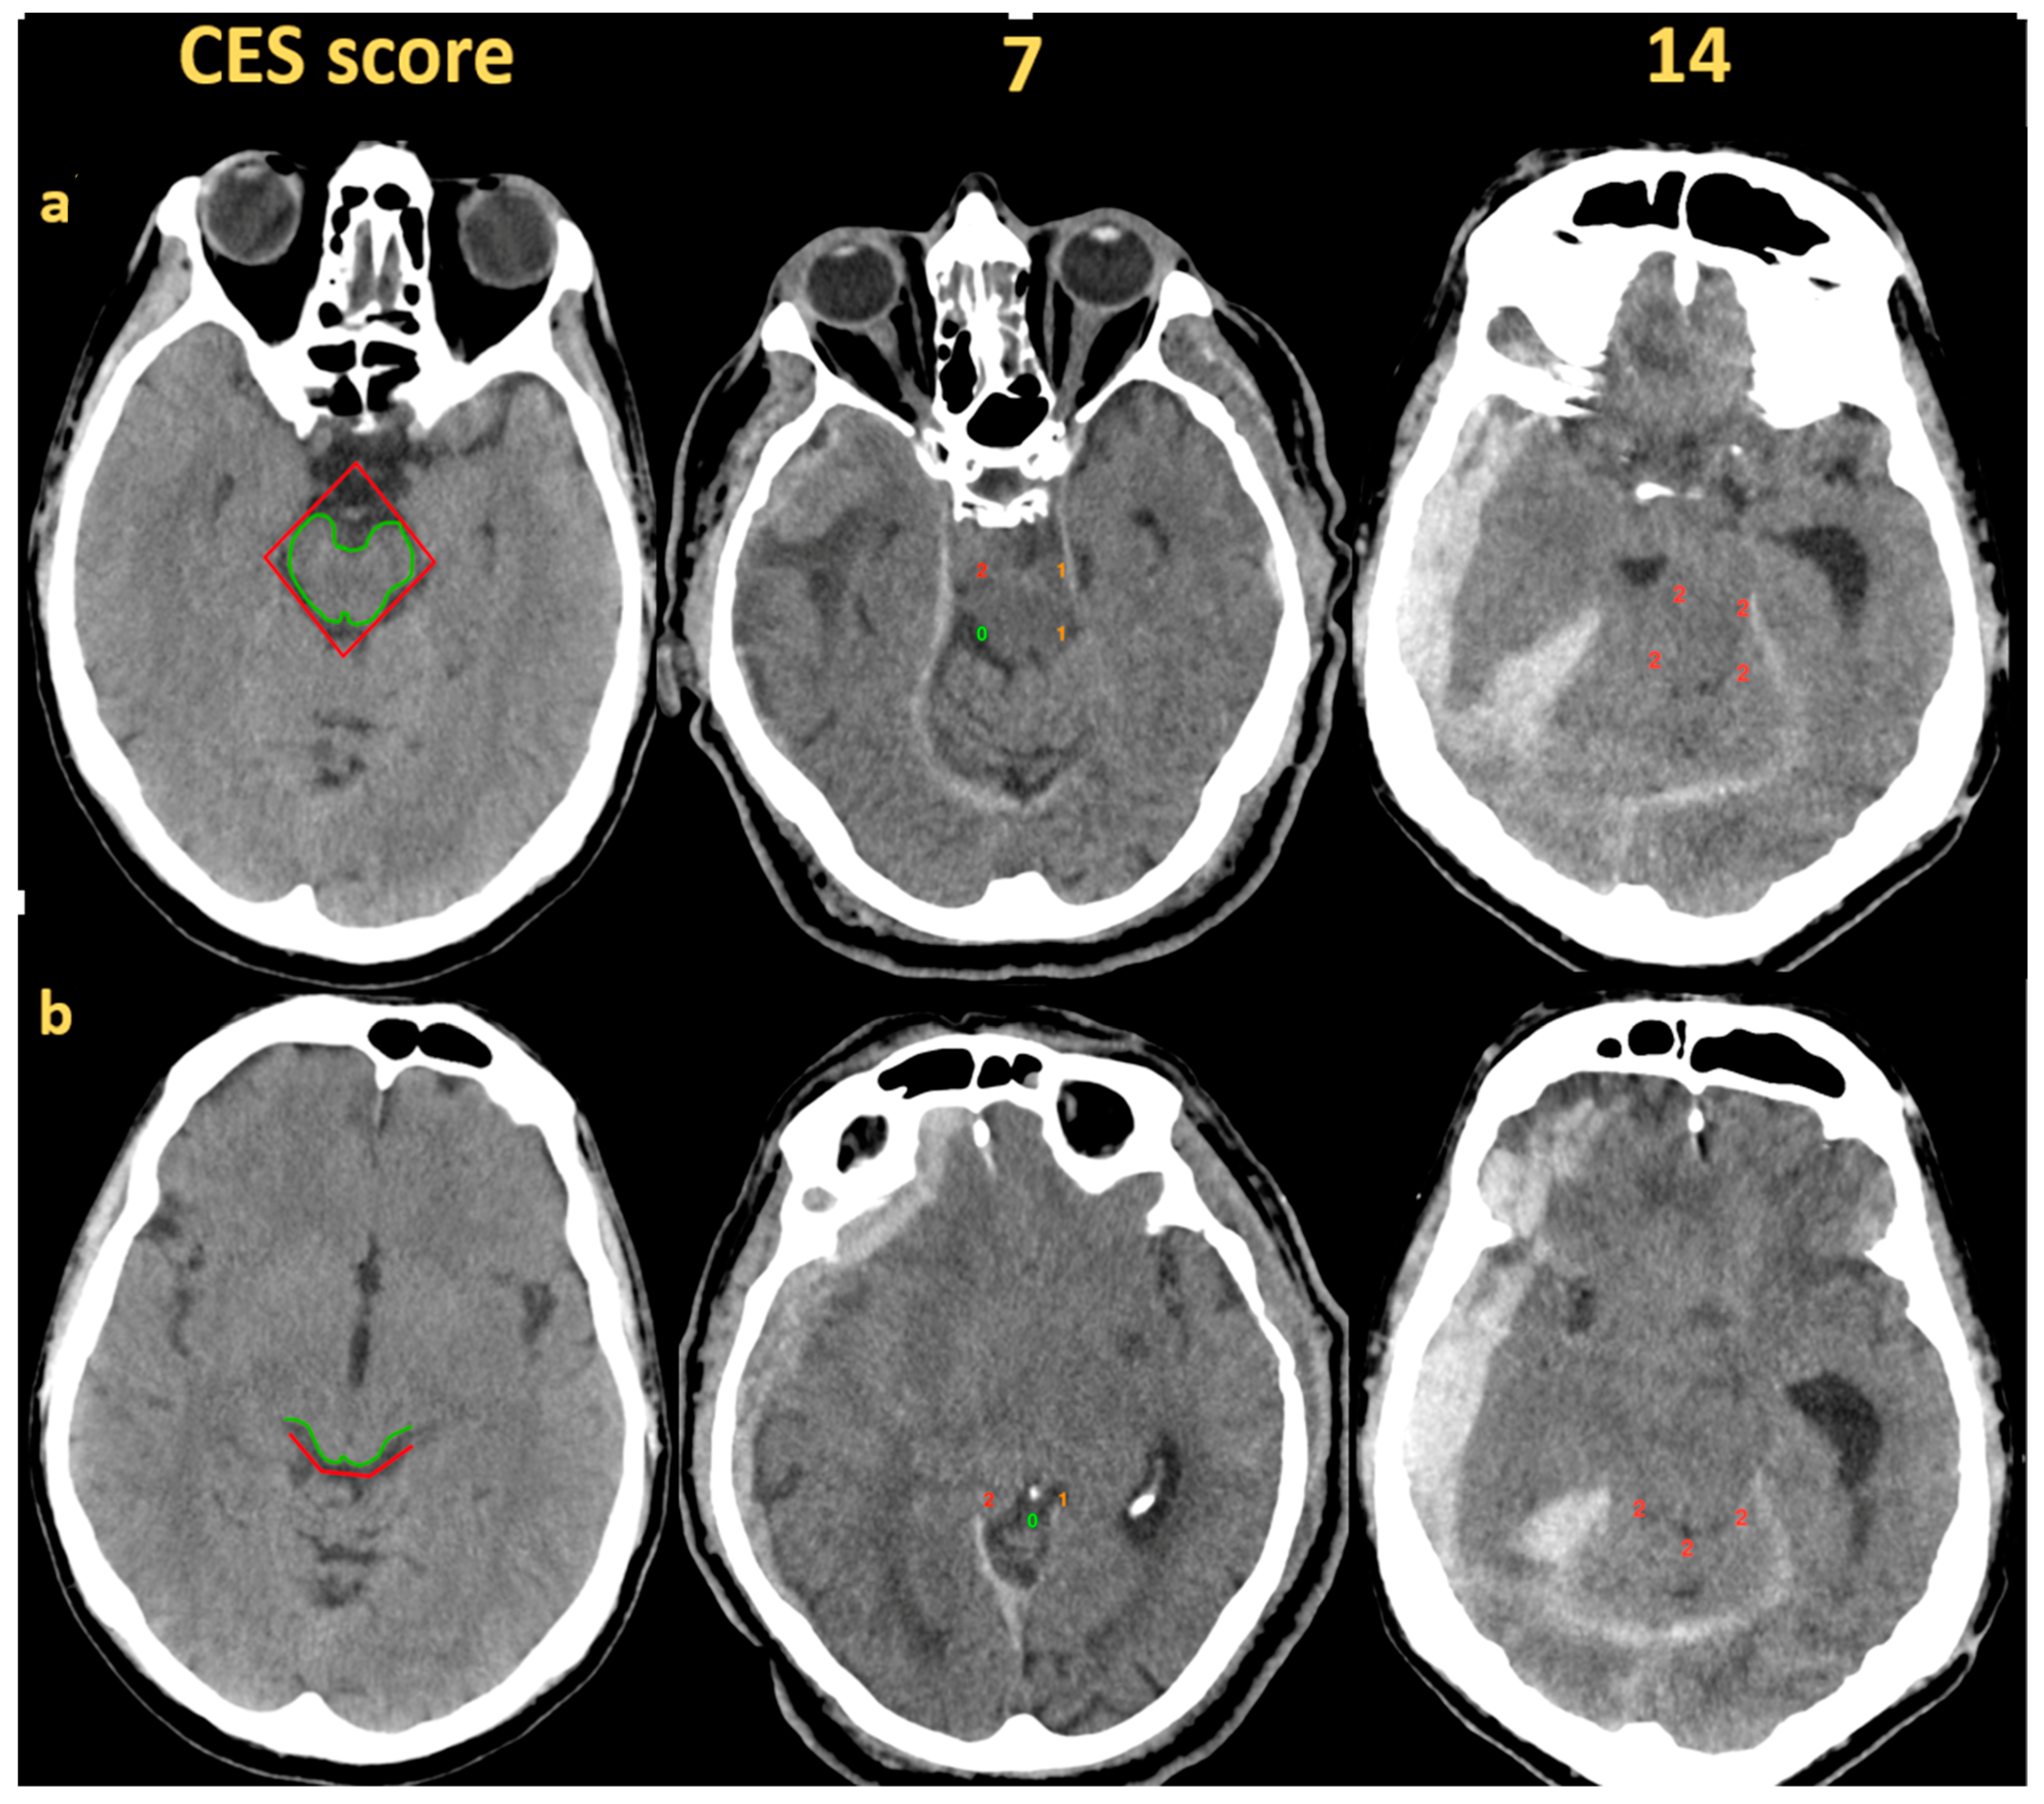

- Juskys, J.; Vilcinis, R.; Piliponis, L.; Tamasauskas, A. Degree Of Basal Cisterns Compression Predicting Mortality and Functional Outcome After Craniotomy and Primary Decompressive Craniectomy in Acute Subdural Hematoma Population. Acta Neurochir. 2023, 165, 4013–4020. [Google Scholar] [CrossRef]

| Preoperative cisternal effacement score | 7 (3–11) | 11 (8–13) | 4 (2–9) | <0.001 |

| Post-operative cisternal effacement score | 2 (1–6) | 4 (2–11) | 2 (0–4) | 0.003 |

| Preoperative cisternal effacement score | 0.78 (0.74–0.82) | <0.001 | 0.80 (0.70–0.91) | <0.001 | 0.8 (0.75–0.85) | <0.001 |

| Preoperative cisternal effacement score | 0.85 (0.79–0.92) | <0.001 | 0.78 (0.66–0.91) | 0.002 | 0.89 (0.81–0.97) | <0.001 |